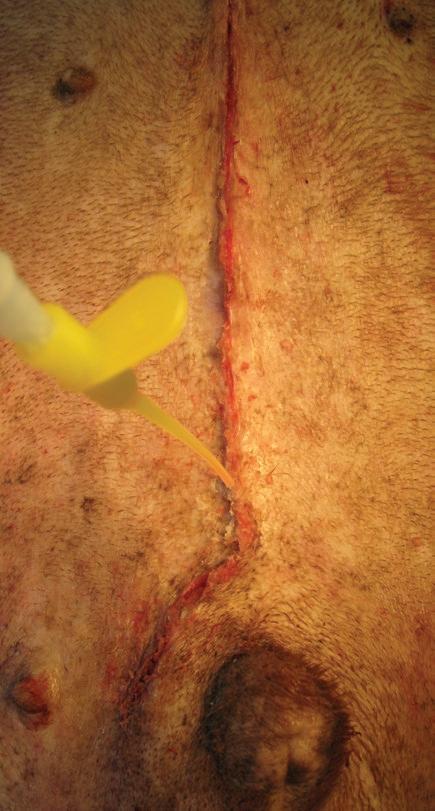

Dermafuse® – Tissue Adhesive

Dermafuse® Tissue Adhesive is a medical adhesive used to bond tissue together following veterinary procedures (i.e. lacerations, abrasions. suture/staple line sealing, tooth extractions, oral surgeries, spaying/neutering and dewclaw removal).

Product contains blue dye to allow user to easily see where product has been applied.

On contact with body tissue, Dermafuse® changes from liquid to solid state by polymerising within seconds to seal the wound.

The Adhesive stops minor bleeding and binds wound edges. Each 3g bottle contains approximately 175 drops.

Use for: Lacerations, Abrasions, Suture/staple line sealing, Tooth extractions, Oral surgeries, Spaying/neutering, Dewclaw removal.